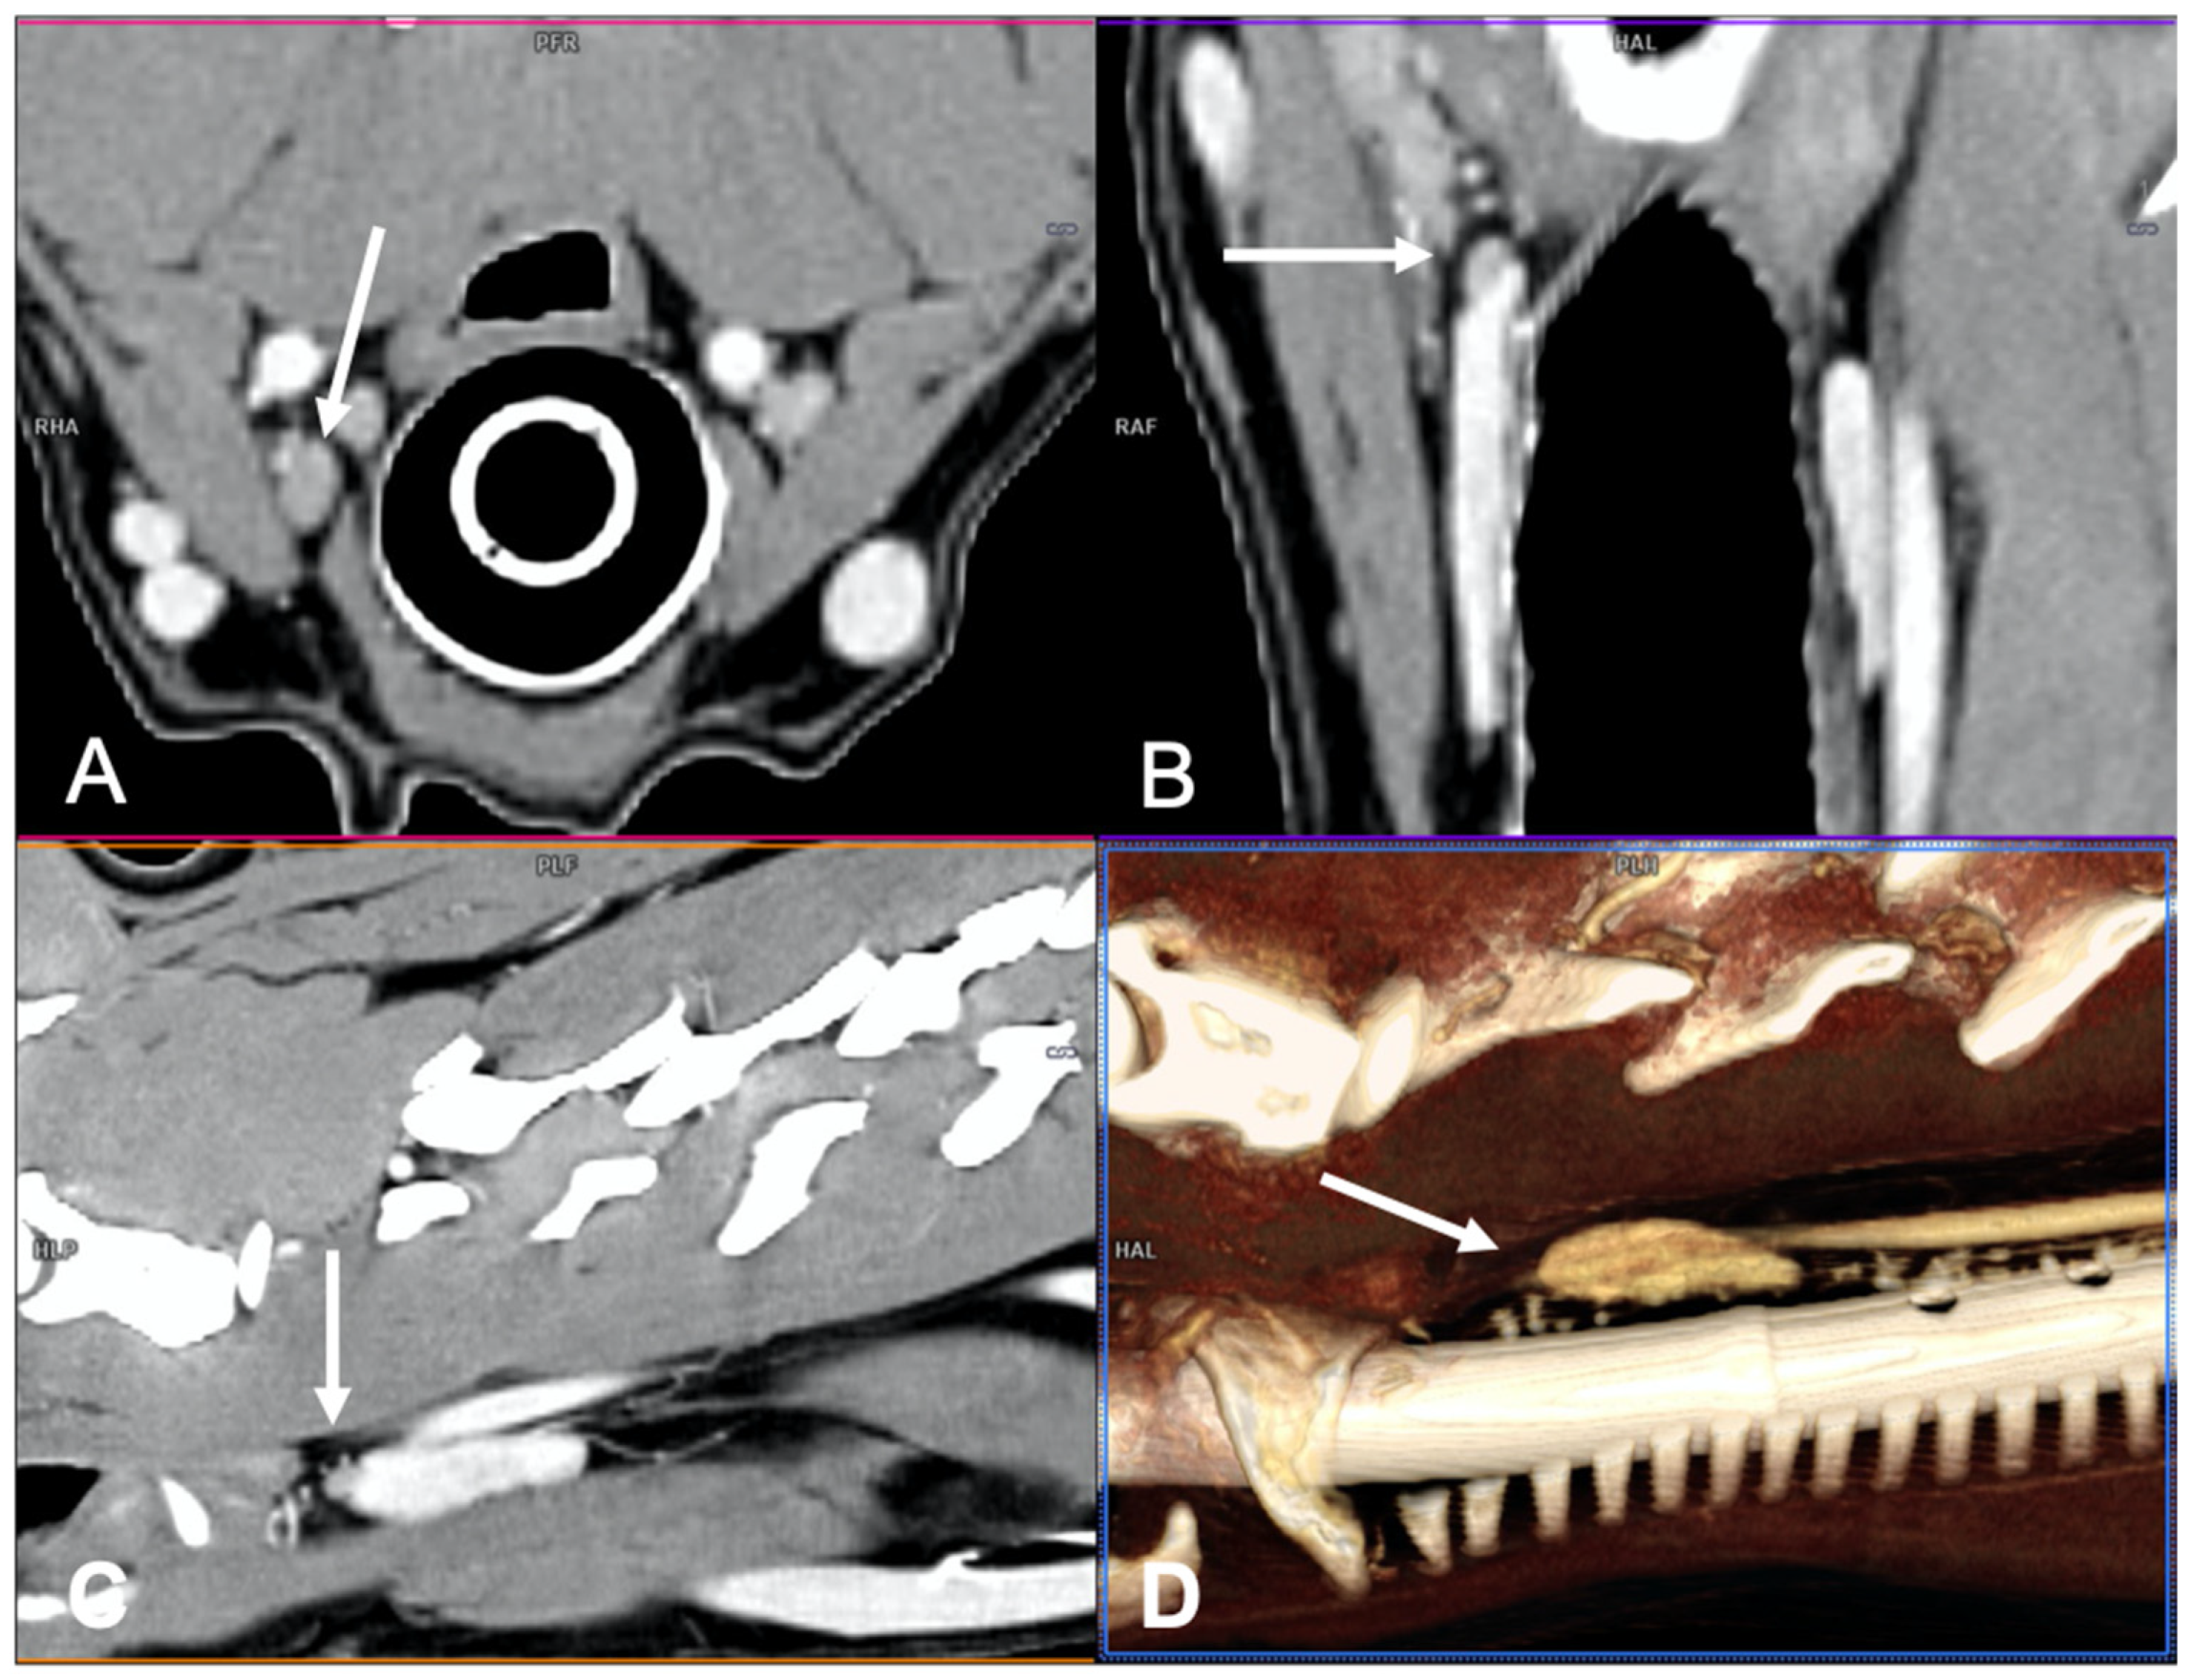

Figure 1.

Visualization of a normal right external parathyroid gland in a dog, post-contrast images. Two different 3D image volume techniques were used: multiplanar reformation (MPR), in which the three orthogonal imaging planes are seen (A) transverse plane; (B) dorsal plane; and (C) sagittal plane, and volume rendering (VR) technique (parasagittal view) (D).